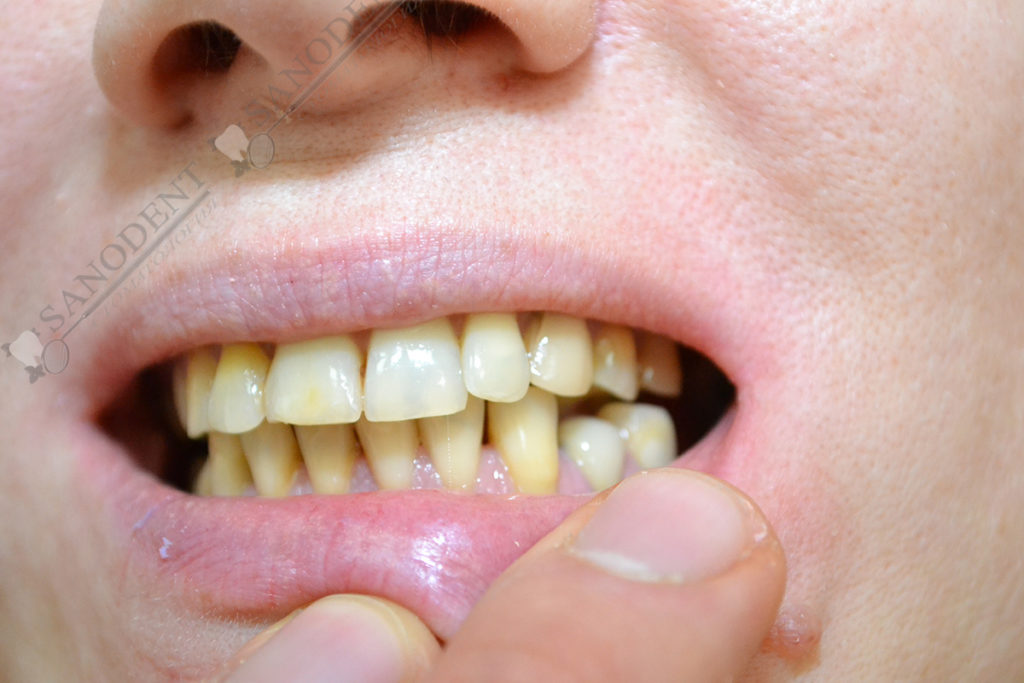

Довольно сложная работа по протезированию ввиду неправильного прикуса пациента и категорического отказа проходить ортодонтическое лечение. Проводилось формирование правильного прилегания коронок к десне . Улучшение эстетики улыбки с помощью керамических виниров.

- до лечения

- искривление зубного ряда

- многочисленные дефекты эмали